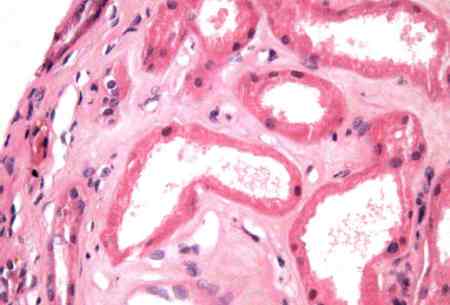

- renal biopsy:

normal-appearing glomeruli under light microscopy with effacement of podocyte foot processes under electron microscopy